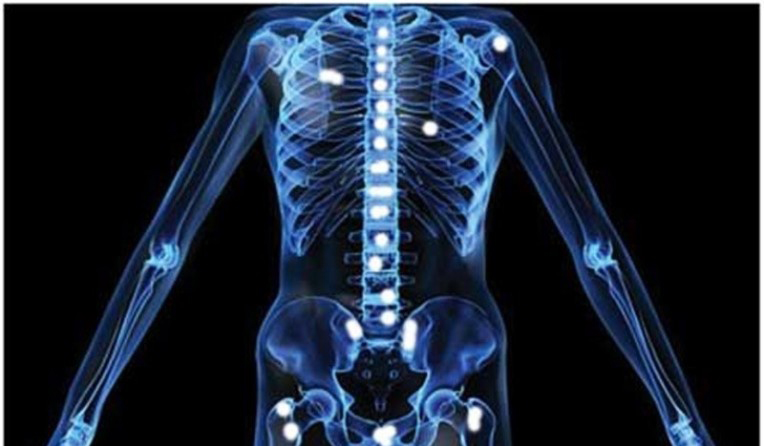

- 허리, 엉덩이, 다리 통증

- 설명: 전립선암은 뼈로 전이가 잘 되는 암입니다. 암세포가 척추, 골반, 허벅지 뼈 등으로 전이되었을 경우, 해당 부위에 지속적이고 심한 통증을 유발합니다. 이는 암이 상당히 진행된 경우에 나타나는 증상입니다.